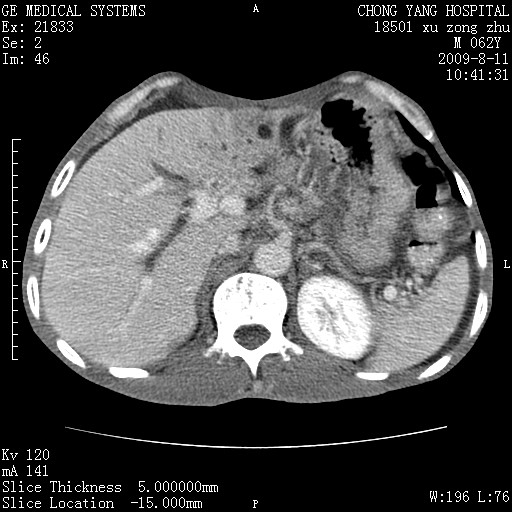

以下是引用杀毒软件在2009-8-11 16:35:00的发言:[br]肝内胆管扩张局限于左叶,胆管内有结石伴肝外胆管结石,胆管壁增厚呈弥漫性并发腹腔积液,胰腺边界模糊。[br][br]考虑---胆总管及肝内胆管结石继发胆管炎及胰腺炎,左肾下极囊肿,腹水。

以下是引用zjzjr在2009-8-11 17:35:00的发言:[br]肝内胆管扩张局限于左叶,胆管内有结石伴肝外胆管结石,胆管壁增厚呈弥漫性并发腹腔积液。[br][br]考虑---胆总管及肝内胆管结石继发胆管炎,左肾下极囊肿,腹水。